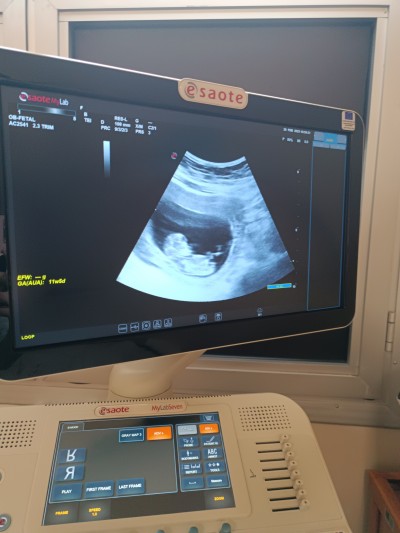

Cinsiyet tahmini yapar mısınız şimdiden tesekkurlerrr

Gebelik haftası 12

Kiz  bacak  arasi  bosss hatta  yaninda  bacagin plesenta  var  kese  kafa  yapisina gore  cinsiyet  tahmini   olmaz boyle birdey  olcaz  doktorlsr  hergun bebem  goruyor   bilirdi  bacak  arasi  onrmli  en net  15  hafta  benim  gordugum  suan  duz  cikimti  yok